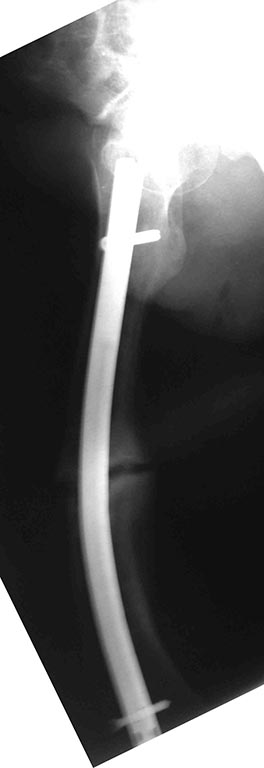

[Ortho] перелом бедра с исходной деформацией

Сегодняшние снимки из операционной, подходящей пластины не было, а

гвоздь был.